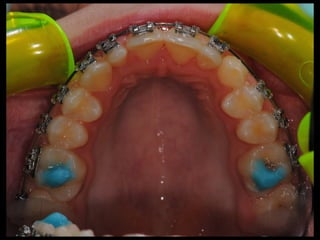

Hybrid functional appliance have to be used to correct the asymmetry.

The goal would be to disctract the left condyle from the fossa, create an open

bite in the left side to allow vertical dentoalveolar growth while restricting to

some extent the dentoalveolar growth with the bite plane in the left side.

!

Hybrid of bionator in the right side and Frankell II in the left side.